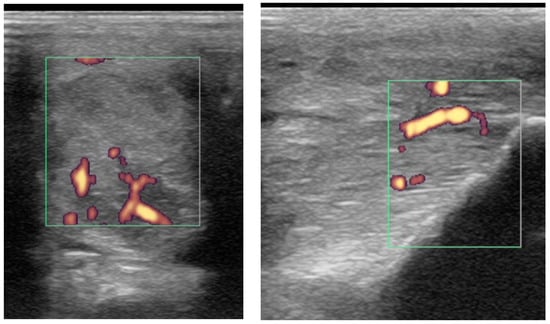

2.3.2. Power Doppler Examination

Power Doppler examination was included for horses examined from 2014 onwards to monitor vascular activity. This was initially performed in a standing position, to assess hypoechoic regions compatible with blood vessels, although if no signal was detected, the examination was repeated in a non-weightbearing position. Hypoechoic regions were assessed in several orientations and for at least two minutes and with the minimal pressure required to achieve adequate image quality, but to avoid false negative results by excessive compression. No sedation was used for examinations to avoid interference with the detection of neovascularisation. Only vascularisation inside a branch was considered a positive finding. If a positive signal was detected, a video clip of several seconds with variable angles was recorded. Power Doppler signal was classified as absent, mild, moderate or severe (Figure 1).

Figure 1. Transverse power Doppler ultrasonographic images of suspensory ligament branches representing the grades of power Doppler signal, from absent to severe, adapted from Szkudlarek et al. [24]. In all images, palmar is to the right.

Power Doppler examination was performed in 62/89 branches (67.4%). Doppler signal was present in 59/62 (95.2%) branches (Figure 5, Figure 6, Figure 7 and Figure 8) and absent in three branches. At the initial examination, Doppler signal was classified as mild in 22/62 branches (35.5%), moderate in 25/62 (40.3%) and severe in 12/62 (19.4%) branches. Doppler signals persisted in follow-up examinations, despite treatment, in 17/62 branches (27.4%) (Figure 7).